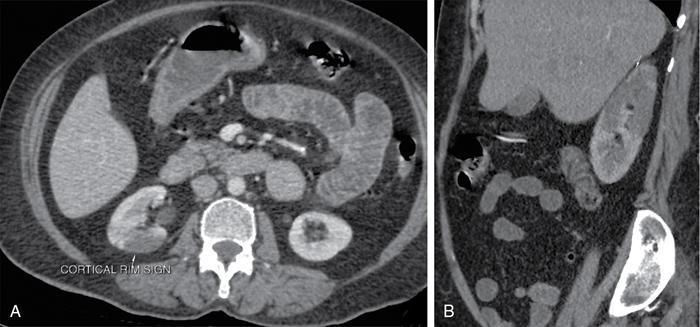

• Focal infarcts are seen as wedge-shaped nonenhancing areas in the renal parenchyma (Fig. 10.18.1.7).

• ‘Cortical rim sign’ (Fig. 10.18.1.7) refers to thin rim of preserved subcortical enhancement in patients with renal infarcts due to renal capsular perforating vessels.

Fig. 10.18.1.7 Renal infarct with cortical rim sign on CT.